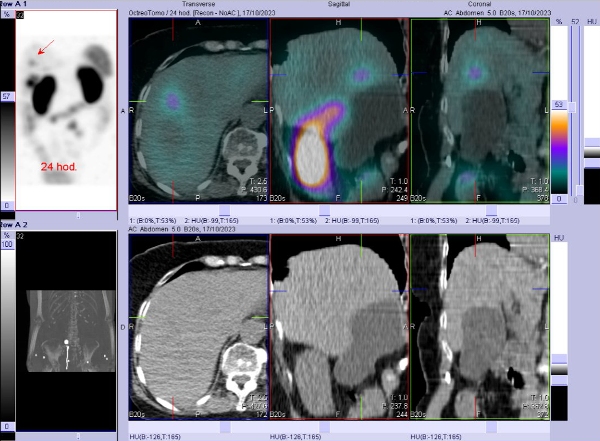

/ Obr. č. 4: Fúze SPECT/CT břicha a pánve 24 hod. po aplikaci OctreoScanu. Zaměřeno na ložisko v pravém jaterním laloku.

/ Obr. č. 5: Fúze SPECT/CT břicha a pánve 24 hod. po aplikaci OctreoScanu. Zaměřeno na kámen ve žlučníku.